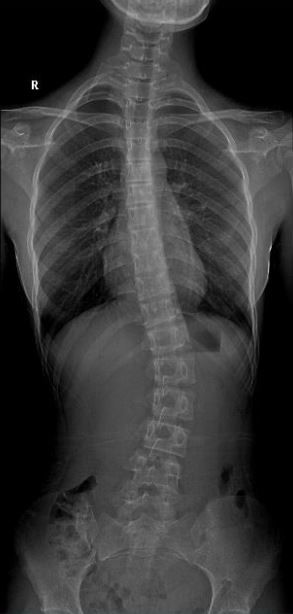

女 16岁

脊柱侧弯畸形

AEC 80KV

脊柱侧弯畸矫形术前检查

通过全景拼接图像可以清晰显示脊柱侧弯的具体细节,为矫形手术提供更详尽的资料。